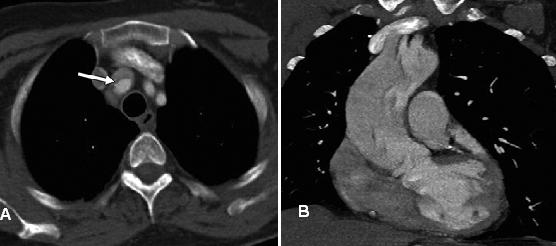

Hình 13: Bóc tách động mạch chủ Stanford type A. (a) Hình axial qua ngực thấy tràn dịch màng tim tăng đậm độ (mũi tên) phù hợp với tràn máu màng tim. (b, c) Hình axial qua ngực ở bệnh nhân khác cho thấy tràn dịch màng tim đậm độ cao phù hợp với tràn máu màng tim, cũng như tràn máu màng phổi trái. Vành bóc tách thấy rõ ở động mạch chủ xuống. (d) Hình MIP sagittal thấy vành bóc tách ở phía xa của động mạch dưới đòn trái (mũi tên) cùng với tràn máu màng tim và màng phổi.